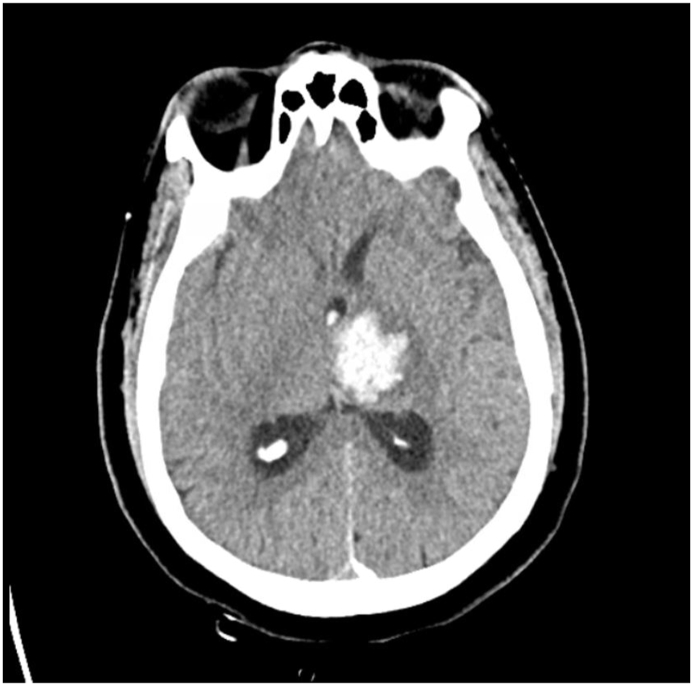

A 56-year-old man was brought to the hospital in an unresponsive state. His Glasgow Coma Scale on presentation was 6. He was afebrile with a pulse of 93/min and a BP of 182/108 mm Hg. On neurological examination, his pupils were reactive to light with positive corneal and gag reflex. He withdrew his left upper and lower extremity to pain but had a weak response on the right side. He was intubated for airway protection. Computed tomography (CT) brain showed a left thalamic hemorrhage (Fig. 1) with edema and mass effect on the 3rd ventricle, intraventricular extension of hemorrhage, and hydrocephalus. An external ventricular drain was placed successfully with adequate drainage. He was started on hypertonic saline with a serum sodium goal of 150–160 mmol/L. He was placed on video electroencephalography (vEEG) which did not reveal any epileptiform activity and was discontinued after two days. Magnetic resonance imaging (MRI) on day 2 showed improvement in hydrocephalus but there was a 1 cm midline shift of the septum pellucidum without any transtentorial herniation. He self-extubated himself on day 4 of his admission and underwent a tracheostomy due to a difficult re-intubation. On day 5, repeat CT brain showed improvement of midline shift to 3 mm. Therefore, the hypertonic saline was switched to normal saline. On day 7 of the admission, the patient developed persistent abdominal jerks. These jerks were occurring every 3–4 seconds and would last for hours with brief periods of remission. Repeat CT brain was unchanged. His sodium was 145 mmol/L, potassium was 4.3 mmol/L and calcium was 7.6 mg/dL. His albumin was 2.5 g/dL, therefore his corrected calcium level was 8.5 mg/dL. He did not have any evidence of pneumonia on a chest X-ray. CT of the abdomen did not reveal any acute process. He was started on levetiracetam 1000 mg IV bid for presumed myoclonus and it was then increased to 1500 mg IV BID without any improvement of symptoms. The patient was also placed on vEEG again which did not reveal any epileptiform abnormality but did show an electromyography (EMG) artifact (Video 1). It was determined that these jerks were likely hiccups. The levetiracetam was discontinued. Metoclopramide 10 mg IV was tried without any benefit. He was then started on baclofen 10 mg PO TID which resulted in a significant improvement in hiccups. Over the next week, the patient continued to gradually improve. He was then discharged home with outpatient rehabilitation. At the time of discharge, he did not have any focal weakness. His cranial nerve examination was normal. He had mildly diminished sensations to temperature and light touch in the right upper and lower extremities. His deep tendon reflexes were 2/4 in all extremities, and he did not exhibit any signs of cerebellar dysfunction.

Fig. 1.

Computed tomography of the brain showing a left thalamic hemorrhage.